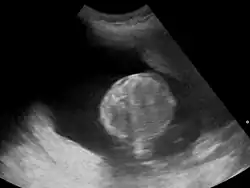

Polyhydramnios is a medical condition describing an excess of amniotic fluid in the amniotic sac. It is seen in about 1% of pregnancies.[1][2][3] It is typically diagnosed when the amniotic fluid index (AFI) is greater than 24 cm.[4][5] There are two clinical varieties of polyhydramnios: chronic polyhydramnios where excess amniotic fluid accumulates gradually, and acute polyhydramnios where excess amniotic fluid collects rapidly.

Diagnosis

During the pregnancy, certain clinical signs may suggest polyhydramnios. In the mother, the physician may observe increased abdominal size out of proportion for her weight gain and gestation age, uterine size that outpaces gestational age, shiny skin with stria (seen mostly in severe polyhydramnios), dyspnea, and chest heaviness. When examining the fetus, faint fetal heart sounds are also an important clinical sign of this condition.